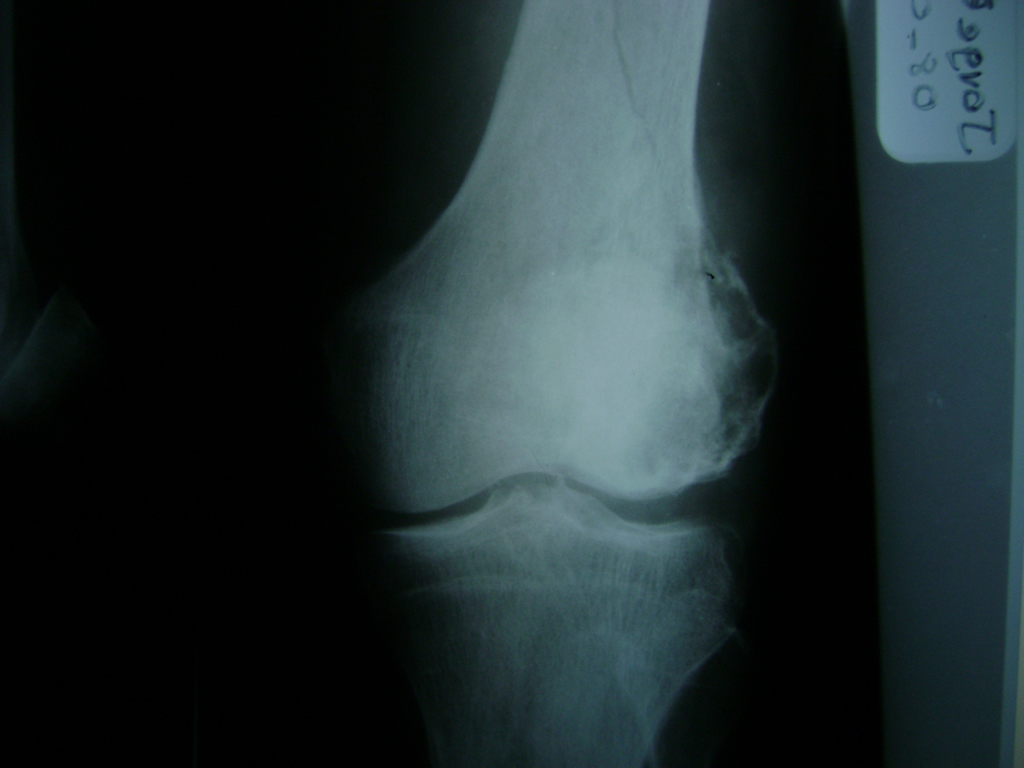

Cirugías de Codo - Rodilla

La artroscopia de rodilla es un cirugía en el cual la estructura interna de la articulación es examinada ya sea para realizar un diagnostico o para realizar un tratamiento, este procedimiento se realiza utilizando un instrumento parecido a un pequeño tubo llamado artroscopio.